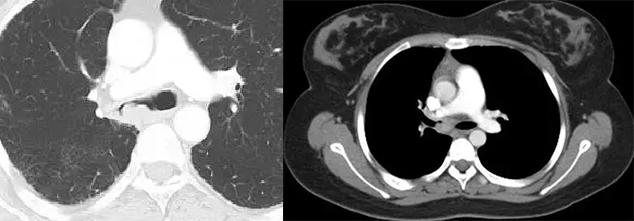

转移瘤并发气胸

肺转移瘤并发气胸罕见。多见于肉瘤特别是骨肉瘤或滑膜肉瘤肺转移,骨肉瘤病人发生气胸时应高度怀疑转移,也见于具有侵袭性和坏死特点的肉瘤样肿瘤。CT 除显示气胸外,多可显示肺内转移灶,且多在肺外围。其发生机制可能与原发肺癌引发气胸相似,即①肺表面的转移瘤液化坏死,发生穿孔,与胸膜腔相通形成气胸;②较大的支气管黏膜下转移影响气道,形成活瓣致管腔不全阻塞,远端肺泡过度膨胀破裂形成气胸。

肿瘤性动脉栓塞

肿瘤性栓塞位于血管内、无血管外增殖。增强主肺动脉或叶段肺动脉充盈缺损、增强后见强化为其特点。小动脉分支突然截断和扭曲。周围型肺动脉内瘤栓常位于胸膜下,肺动脉分支局部增粗、扭曲,可见树芽征。大量瘤细胞栓塞肺小动脉或毛细血管时可仅显示肺动脉高压征象。

肉瘤样癌并肿瘤性动脉栓塞、自发性气胸。

支气管内膜转移

CT 示支气管内息肉样肿物,支气管壁增厚,管腔狭窄,可形成黏液栓、合并阻塞性肺炎或肺不张。其发生机制可能是肿瘤细胞通过淋巴或血行直接播散转移至支气管壁、淋巴结或肺实质内,肿瘤细胞沿支气管树生长并突破支气管壁形成腔内病灶。

两图分别为直肠癌支气管内膜转移、软骨肉瘤支气管内膜转移。